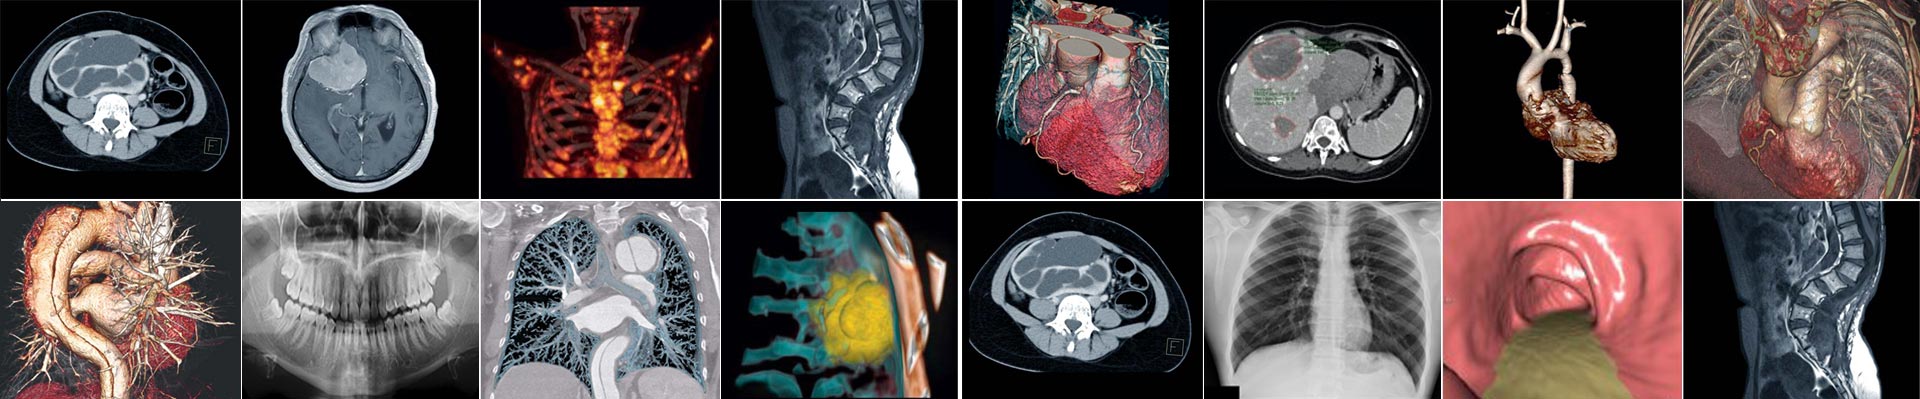

يعتبر التصوير الطبي وسيلة استقصائية هامة تساعد الأطباء للوصول للتشخيص الأكيد للأمراض

و ان التقنيات المتطورة و النوعية العالية للتصوير تشكل عاملا هاما في المحافظة على صحة المرضى و التشخيص الدقيق للآفات المرضية .